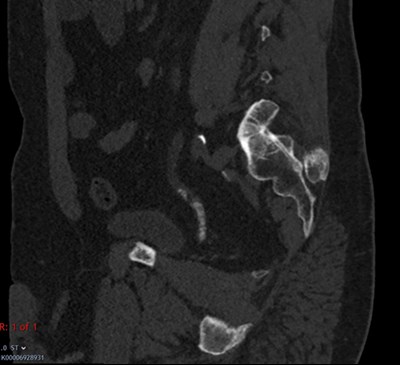

Figure 3.

3. Describe the complication demonstrated in Figure 3.

3. Figure 3 is a sagittal reconstruction of a CT KUB in the bone window demonstrating a column of small stone fragments within the left lower ureter extending 3cm in length, with mild upstream hydroureter in keeping with steinstrasse.

Steinstrasse, the German word for ‘Stone street’, describes a possible complication of ESWL where a column of stone fragments cause obstruction. The most common site for this fragment column is the distal ureter (64% of cases). The incidence of steinstrasse has greatly decreased from 20% to 6% due to a refinement in ESWL technique [8]. Management options for steinstrasse are similar to that of a primary obstructing calculus.